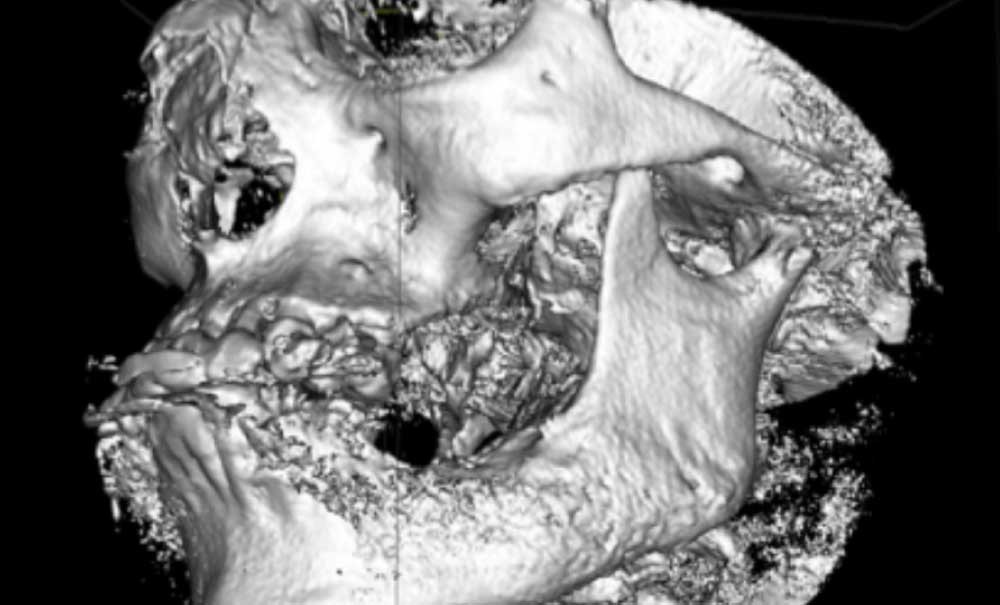

L’examen radiologique (scanner ou tomographie a faisceau conique) est très évocateur. Il montre un épaississement périosté avec « aspect mixte » de l’os médullaire et des « perforations corticales ».

L’ostéomyélite passe par plusieurs stades au cours de son évolution. Au début, les zones d’ostéolyse et de sclérose sont invisibles radiologiquement…